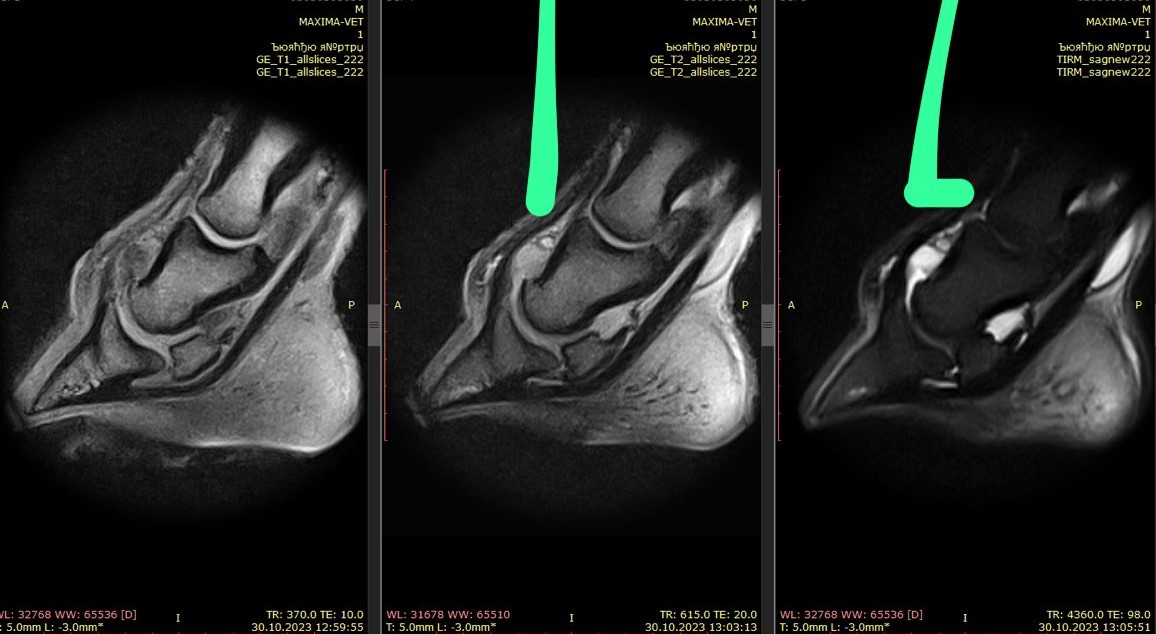

МРТ-исследование: разлитой синовит копытного сустава, отек копытной кости по месту крепления медиальной коллатеральной связки, в Т2 режиме структуры медиальной коллатеральной связки с гиперинтенсивным сигналом.

ДИАГНОЗ: энтезопатия медиальной коллатеральной связки копытного сустава;

артрит копытного сустава.

После МРТ-исследования были даны рекомендации: внутрисуставные инъекции,

курс системных препаратов, шаговая нагрузка в течение 2-х месяцев.

Далее повторный осмотр.